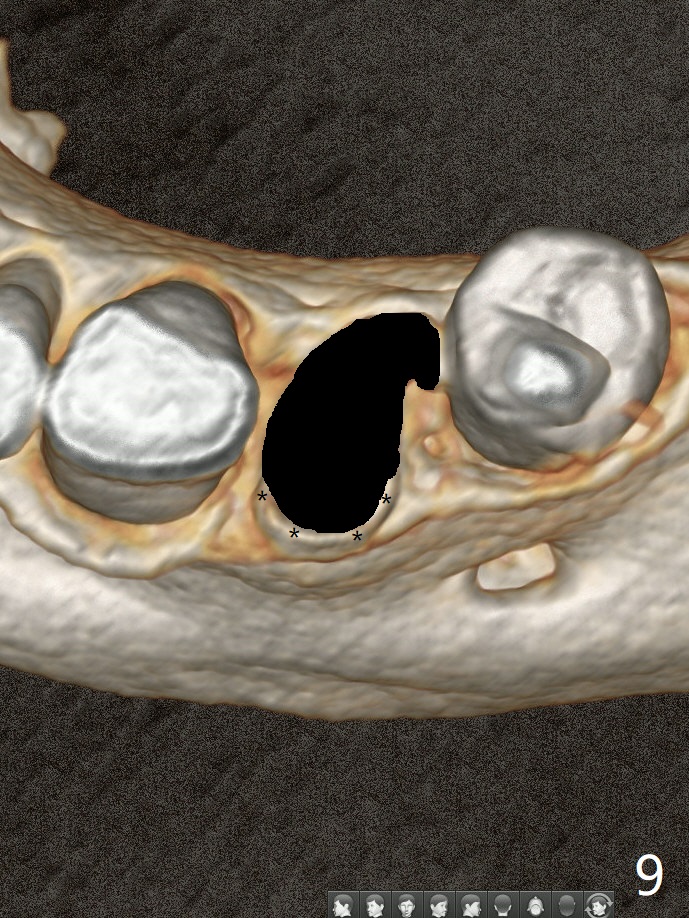

A 52-year-old man chooses to take care of the teeth #21 and 29 first due to finance (Fig.1). The implant diameter should not be too large because of the moderate mesiodistal space (Fig.2,3). Since the buccal plate of #21 is indistinct (socket shield will be done), the implant should be a little more lingually placed than the design in Fig.3, although the implant placement level seems to be acceptable. Socket shield seems to be necessary.